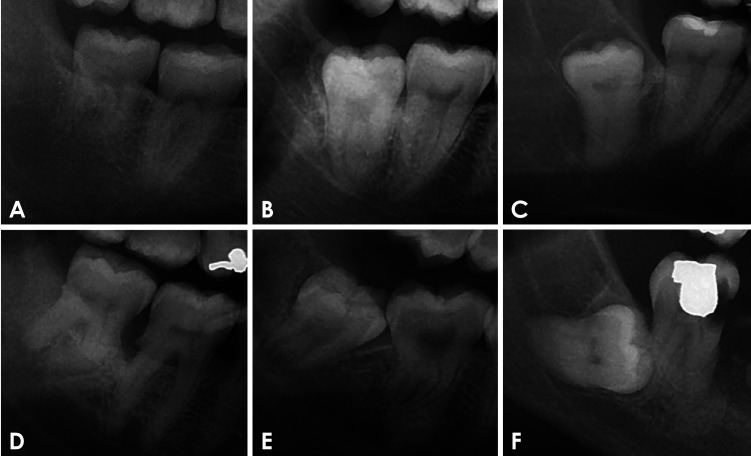

Abstract Image